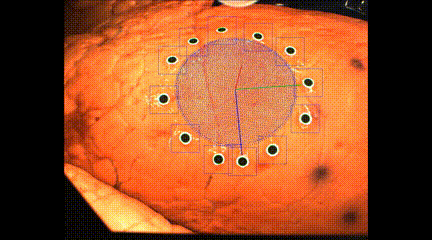

在这项研究中,研究人员将猪肺作为实验对象,使用运动捕捉跟踪标记方法,就像在电影中使用的那样来创建特殊效果。这种方法是将视觉传感系统与3D打印机集成在一起来跟踪随时间变化的3D几何形状,从而在可变形的肺部上制造电子柔性传感器。

1. 首先从预先扫描的数据集中离线学习了表面几何图形的低维参数模型,以降低后续在线计算的复杂度;

2.在挤出机头上安装了两个机器视觉摄像机,通过相机实时测量的一组标记来估计离线学习模型中的参数,从而在线调整了打印刀头路径的几何形状。